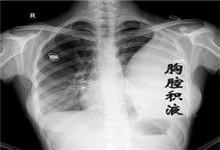

恶性胸腔积液是一种由恶性肿瘤导致的胸腔内疾病。几乎所有的肿瘤都可转移至胸膜,导致恶性胸腔积液。肺癌、乳腺癌、淋巴瘤是最常见的三大原因。胸膜原发性弥漫性恶性间皮瘤也是引起恶性胸腔积液的重要原因。恶性胸腔积液大部分患者多为肿瘤晚期的表现及肺受压迫的表现,如体重下降、消瘦、口唇面部苍白、胸闷、气短、进行性加重的呼吸困难、胸痛、干咳等。恶性胸腔积液的主要治疗方法是手术治疗、药物治疗及引流治疗。恶性胸腔积液可影响呼吸,引起胸痛,甚至危及生命。一旦肺癌或者肺外肿瘤出现了恶性胸腔积液,病程已属晚期,患者已很难治愈,预后较差,积极有效治疗可改善症状,减轻痛苦。